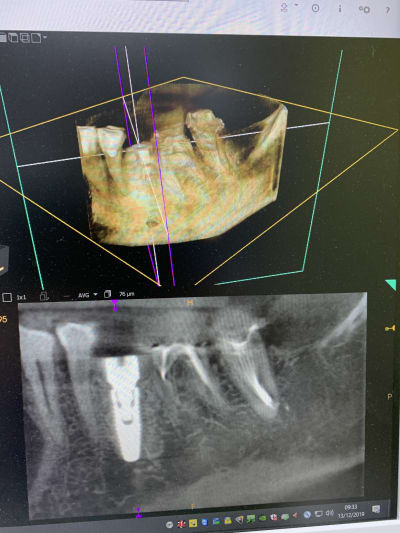

Il y a vraiment des différences de dingue entre les machines !

Les images 3 et 4, les images 6 et 7 sont prises à quelques années d’intervalles.

La machine de 2008 fait très peu d’artefacts, celle de 2018 énormément. Elle à le mar pour les « supprimer », mais ça n’arrange rien !

Les artefacts métalliques sont bien différents selon les machines.

A l’adf on me dit « regardez on voit même les spires des implants », avec ma bécanne de 2008 je vois les spires des vis dans les implants, les têtes de vis... je n’ai rien vu d’équivalent sur les machines récentes.

Regardez comme les tenons sont bien trop larges à la radio !

Les implants sont de gros pâtés blancs...